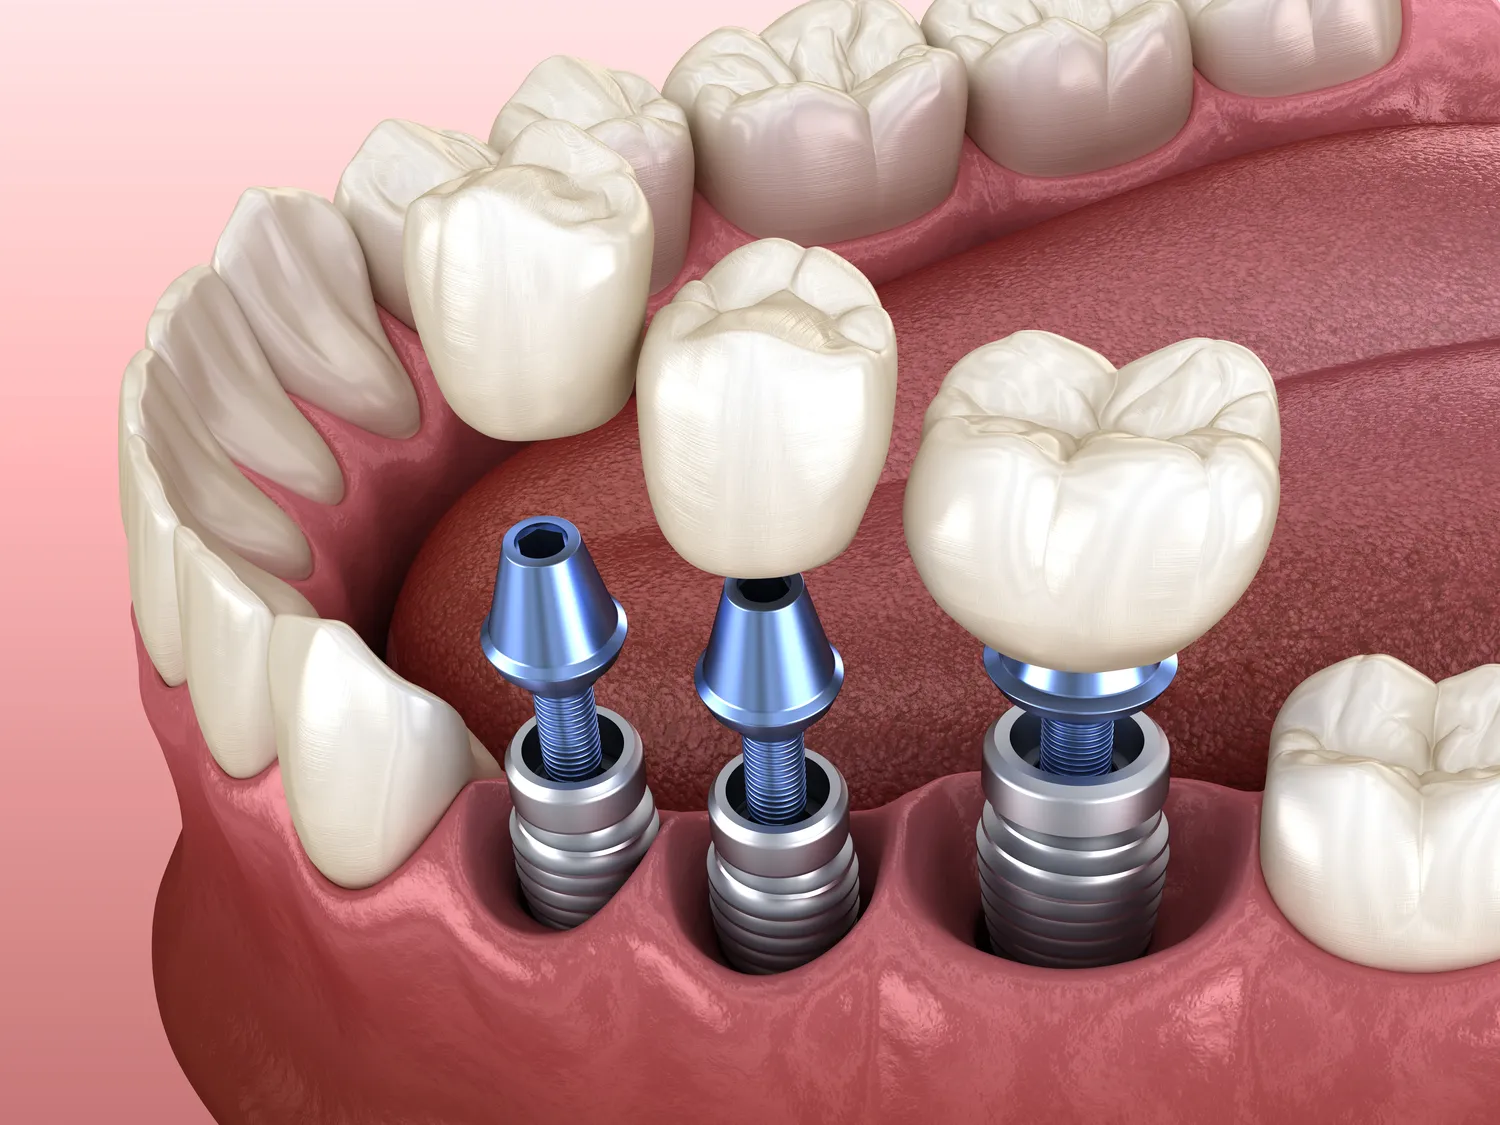

Implantologia stomatologiczna rozwija się w szybkim tempie, a nowe technologie wprowadzane na rynek znacząco poprawiają komfort pacjentów oraz efektywność zabiegów. Jednym z najnowszych osiągnięć jest zastosowanie technologii cyfrowej w planowaniu zabiegów implantologicznych. Dzięki skanowaniu 3D możliwe jest precyzyjne zaplanowanie miejsca wszczepienia implantu oraz ocena stanu kości pacjenta. To pozwala na uniknięcie wielu potencjalnych problemów i zwiększa szanse na sukces całego zabiegu. Kolejną innowacją są implanty wykonane z materiałów biokompatybilnych, które lepiej integrują się z tkankami kostnymi i zmniejszają ryzyko powikłań. Technologia CAD/CAM umożliwia także produkcję indywidualnych koron protetycznych, co sprawia, że efekt końcowy jest jeszcze bardziej naturalny i estetyczny. Warto również wspomnieć o zastosowaniu laserów w implantologii, które pozwalają na minimalizację bólu oraz szybszą rekonwalescencję pacjentów.

Proces leczenia związany z wszczepieniem implantu zębowego składa się z kilku etapów, które mają kluczowe znaczenie dla jego sukcesu. Pierwszym krokiem jest konsultacja stomatologiczna, podczas której lekarz ocenia stan zdrowia pacjenta oraz wykonuje niezbędne badania diagnostyczne, takie jak zdjęcia rentgenowskie czy tomografia komputerowa. Na podstawie tych informacji lekarz podejmuje decyzję o możliwości wykonania zabiegu oraz planuje jego przebieg. Po zakwalifikowaniu pacjenta do zabiegu następuje etap wszczepienia implantu, który odbywa się w znieczuleniu miejscowym lub ogólnym w zależności od skomplikowania przypadku. Po wszczepieniu implantu konieczne jest odczekanie kilku miesięcy na proces osteointegracji, czyli połączenia implantu z kością szczęki. W tym czasie pacjent powinien przestrzegać zaleceń lekarza dotyczących higieny jamy ustnej oraz diety. Po zakończeniu procesu gojenia następuje etap protetyczny, podczas którego na implancie mocowana jest korona protetyczna lub mostek.